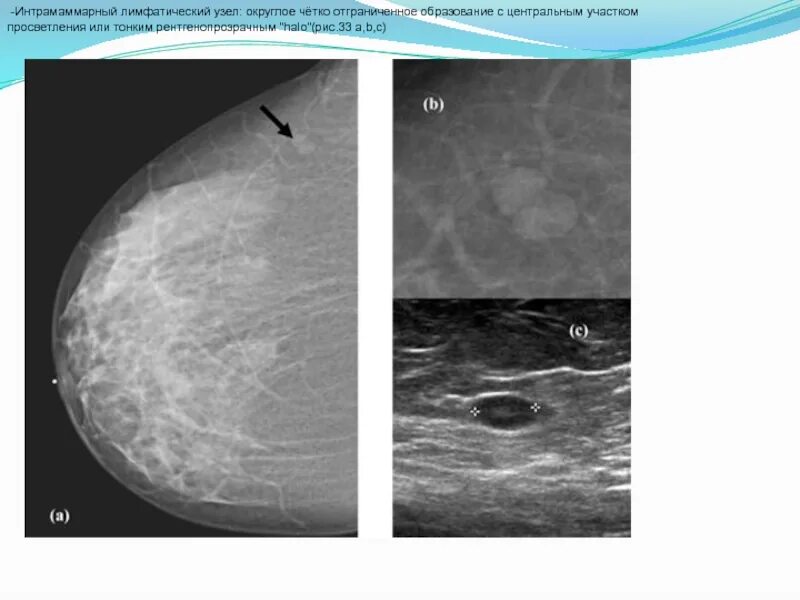

Какой лимфоузел при раке молочной железы